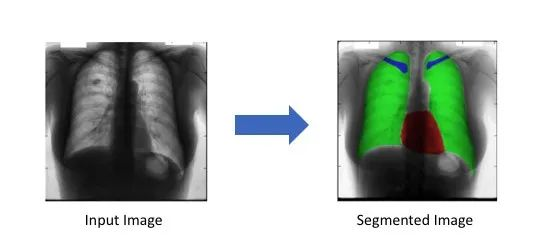

对心脏(红色),肺部(绿色)和锁骨(蓝色)的胸部X光进行了分割